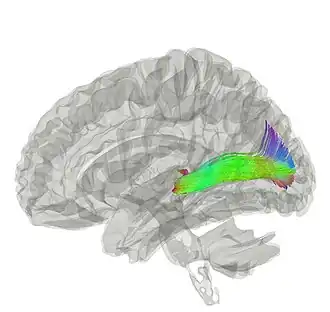

Tractography showing optic radiation | |

In neuroanatomy, the optic radiation (also known as the geniculocalcarine tract, the geniculostriate pathway, and posterior thalamic radiation) are axons from the neurons in the lateral geniculate nucleus to the primary visual cortex. The optic radiation receives blood through deep branches of the middle cerebral artery and posterior cerebral artery.

The optic radiation contains feedforward tracts that transmit visual information (from the retina of the eye) from the geniculate nucleus to the visual cortex, and also feedback tracts from the visual cortex to the neurons in the LGN that project to them.[2] The function of the feedback from the visual cortex back to the LGN is unknown. The optic radiation is activated during working memory tasks.[3] The optic radiations are usually unilateral and commonly vascular in origin. Field defects, therefore, develop abruptly, in contrast to the slow progression of defects associated with tumors.